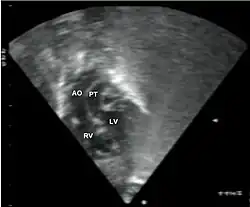

- Echocardiogram: An echocardiogram is an ultrasound of the heart that accurately assesses the heart’s structure and function, and can show the specific features of TGA, if present. This imaging modality allows for the definitive diagnosis of TGA to be made.[3]

Abbreviations: LV and RV=left and right ventricle, PT=pulmonary trunk, VSD=ventricular septal defect, PS=pulmonary stenosis.